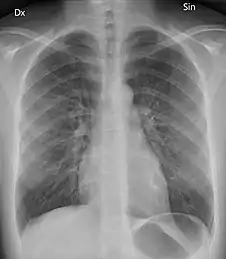

قفسه سینه

مقاله اصلی: رادیوگرافی قفسه سینه

رادیوگرافی قفسه سینه برای تشخیص بسیاری از شرایط شامل دیواره قفسه سینه، از جمله استخوانهای آن و همچنین ساختارهای موجود در حفرههای قفسه سینه از جمله ریهها، قلب و عروق بزرگ استفاده میشود. شرایطی که معمولاً توسط رادیوگرافی قفسه سینه مشخص میشود عبارت اند از ذات الریه، هوای جنبی (وجود هوا یا گاز در پرده جنب)، بیماری ریوی بینابینی، نارسایی قلبی، شکستگی استخوان و فتق حجاب حاجز (هیاتال). بهطور معمول تصویربرداری عمودی قدامی-خلفی (PA) طرح پیشنهادی است. رادیوگرافی قفسه سینه نیز برای یافتن بیماریهای مرتبط با شغلهایی در صنایع مانند صنایع معدن که در آن کارگران در معرض گرد و غبار قرار میگیرند، استفاده میشود.[11] برای بعضی از شرایط قفسه سینه، رادیوگرافی برای آزمایش مناسب است اما برای تشخیص ضعیف است. هنگامی که شرایط یک بیماری بر اساس تصاویر رادیوگرافی قفسه سینه مشکوک میشود، میتوان با تصویربرداری مجدد شرایط قفسه سینه را بهطور قطعی تشخیص داده یا شواهدی را به نفع تشخیص پیشنهاد شده توسط رادیوگرافی اولیه قفسه سینه بدست آورد. به استثنای یک شکستگی دنده که مشکوک به وجود جابجایی است و بنابراین احتمال آسیب به ریهها و دیگر ساختارهای بافت را ایجاد میکند، اشعه ایکس قفسه سینه ضروری نیست زیرا مدیریت بیمار را تغییر نمیدهد.